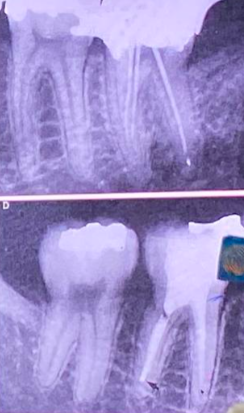

Pre-operative Radiograph

Apical Patency Radiograph

Insert patency file until preliminary working length (PWL)

Take x-ray

Use 27 mm file (IWL/PWL)

0.7 mm extrusion observed

Subtract 1 mm → adjust to 26 mm

Check if file goes beyond apex (nilapas) and if canals are present

Adjust if nilapas

MAF Selection and Radiograph

Insert last file used (MAF)

Take radiograph

Check preparation up to apical third